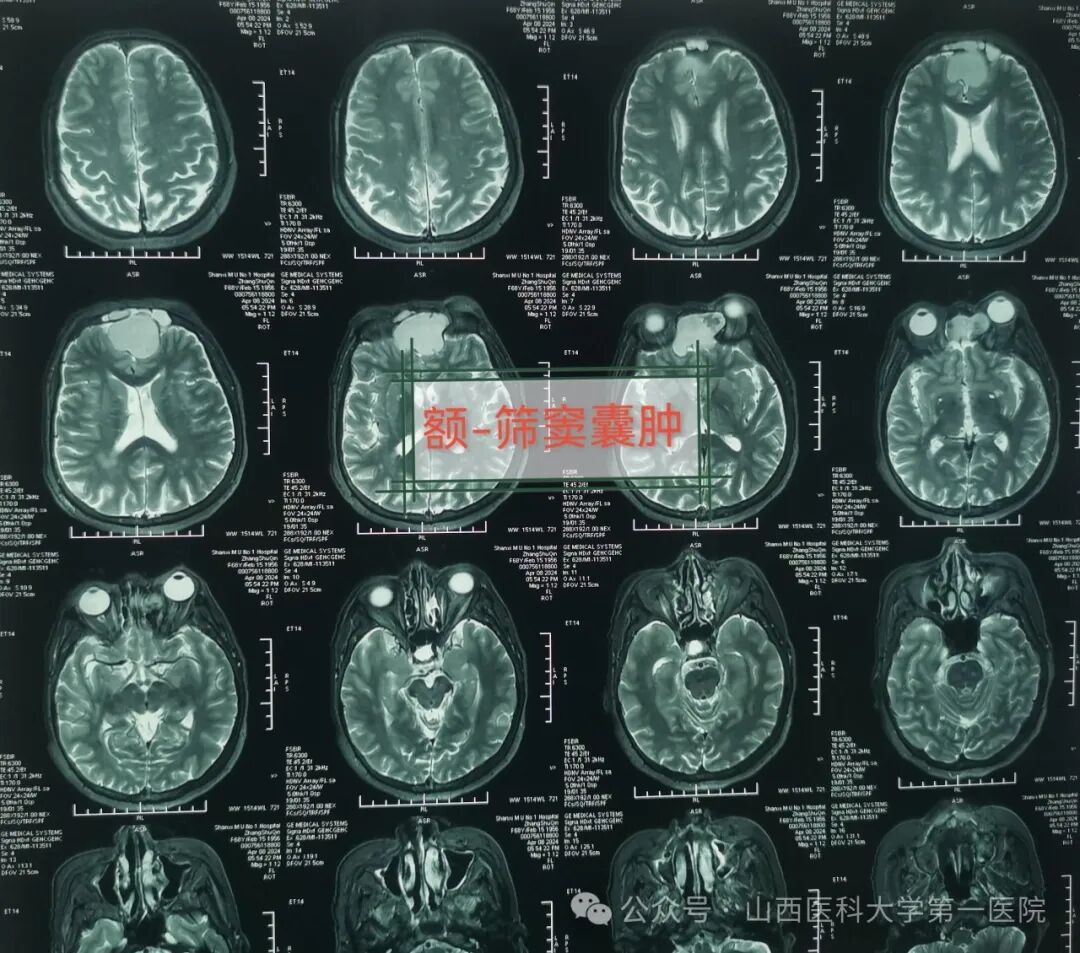

老年女性张某数月来出现头痛、前额部为主,最近发现视物模糊,视力呈进行性下降,且症状越来越加剧,又出现鼻涕中带血丝与嗅觉失灵,于是来到山西医科大学第一医院耳鼻咽喉-头颈外科就诊,经过医生检查后初步诊断为额-筛窦囊肿,侵犯眼眶、前颅底。

医生通过检查发现张某一侧眼球明显向前上方突出,眼球活动受限,单侧视力处于下降状态,鼻窦冠状位CT与MRI提示:额窦、筛窦充满混杂密度阴影,眼眶颅底受压,考虑鼻窦占位性病变引起。耳鼻咽喉-头颈外科主任皇甫辉主刀,术前制定了周密的手术方案,在全麻下行鼻内镜鼻窦囊肿涉眶与颅底根治切除术,术中显露术野,暴露病变组织,发现病变位居单侧筛窦与额窦,已侵犯单侧眼眶及球后与前颅底,病变范围广,内镜下切除鼻腔筛窦与额窦病变组织,开放额窦,切除部分前颅底病变组织,并以人工脑膜修复缺损,最终完整切除病变,手术获得圆满成功。